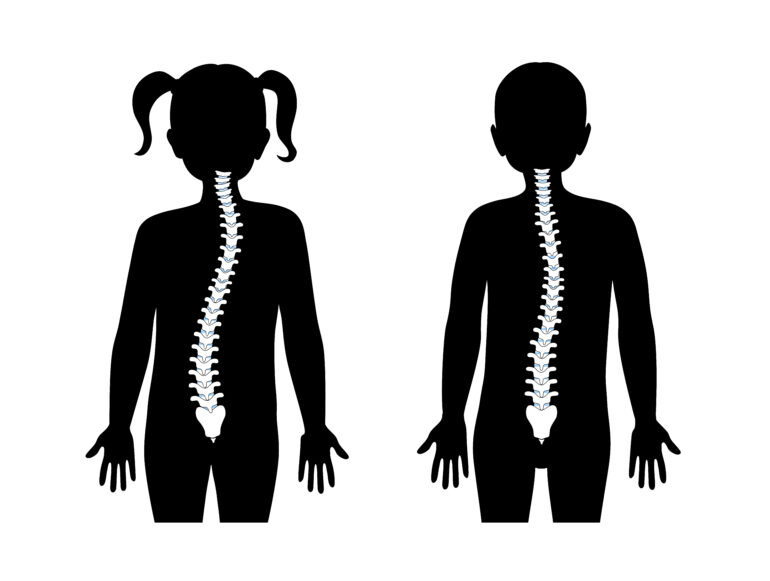

背骨が前や左右に曲がったり、ねじれてしまったりする病気です。 子供でも同じく、背骨が曲がってしまうことがあり、「側弯症」と呼ばれております。子供の場合は前後の変形は乏しく、左右の変形や背骨のねじれがあることが多いです。

その他、小児側弯であったにも関わらず、気づかないまま成長し、加齢と共に重力などの影響で変形が進行してしまう場合があります。昔は学校検診で側弯症を検査することがなかったので、小児側弯と認識されないまま大人になってしまうことがありました。

現在は学校検診で側弯症を診断しますので、側弯症のほとんどは早期に発見することができます。